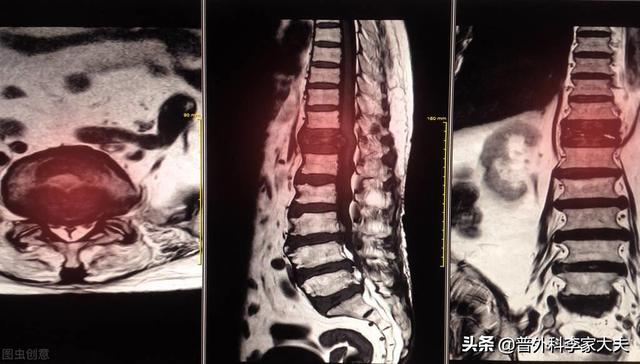

Magnetresonanztomographie von Knochenmetastasen

Nachweis von Knochenmetastasen in der Brustwirbelsäule

Wie bereits erwähnt.dass die Wirbelsäule am anfälligsten für Knochenmetastasen ist.Wenn es also übertragen wird, besteht die Möglichkeit, dass einKompressionsfrakturen des Wirbelkörpersund die Schwellung kann auch auf das Rückenmark übergreifen, wodurch dieKompression des Rückenmarksdie ähnliche Symptome wie eine Nervenwurzelreizung hervorrufen können, wie z. B.Taubheitsgefühl und Schmerzen in den unteren GliedmaßenBei einigen Patienten mit einer Kompression des Rückenmarks besteht die Gefahr, dass sie eineVeränderungen des Gangbildes und Schwäche der Gliedmaßenund bei einigen Patienten, die eine schwere Kompressionsfraktur oder einen Tumor haben, der das Rückenmark stark zusammendrückt, besteht die Gefahr, dass sie eineLähmung

Obwohl es bestimmte Merkmale von Schmerzen bei Patienten mit krebsbedingten Knochenmetastasen gibt, können Sie auch feststellen, dass es einige Symptome gibt, die mit der allgemeinen Krankheit interferieren.Wenn der Patient auftritt, die Knochenmetastasen der Wirbelsäule stimuliert die Nerven, dann ist es leicht für den Arzt oder den Patienten, um die Symptome durch Bandscheibenvorfall induzierten falsch zu diagnostizieren, und zu diesem Zeitpunkt, wie der Patient, der Körper hat Anomalien, sollten wir die Hilfe des Arztes in einer rechtzeitigen Art und Weise zu suchen, und wie der Arzt zu versuchen, mit dem Patienten zu kommunizieren, um einige relativ hohe Qualität der Untersuchung zu tun, versuchen, das Risiko von Knochenmetastasen auszuschließen, wie für die langfristige Rückenschmerzen der älteren Menschen, empfehlen wir oft, dass die MRT anstelle von Röntgen-Untersuchung, und der Patient Rückenschmerzen, der Patient Rückenschmerzen ist sehr hoch. Zum Beispiel empfehlen wir älteren Menschen mit chronischen Kreuzschmerzen oft eine Magnetresonanztomographie (MRT) anstelle einer Röntgenuntersuchung.